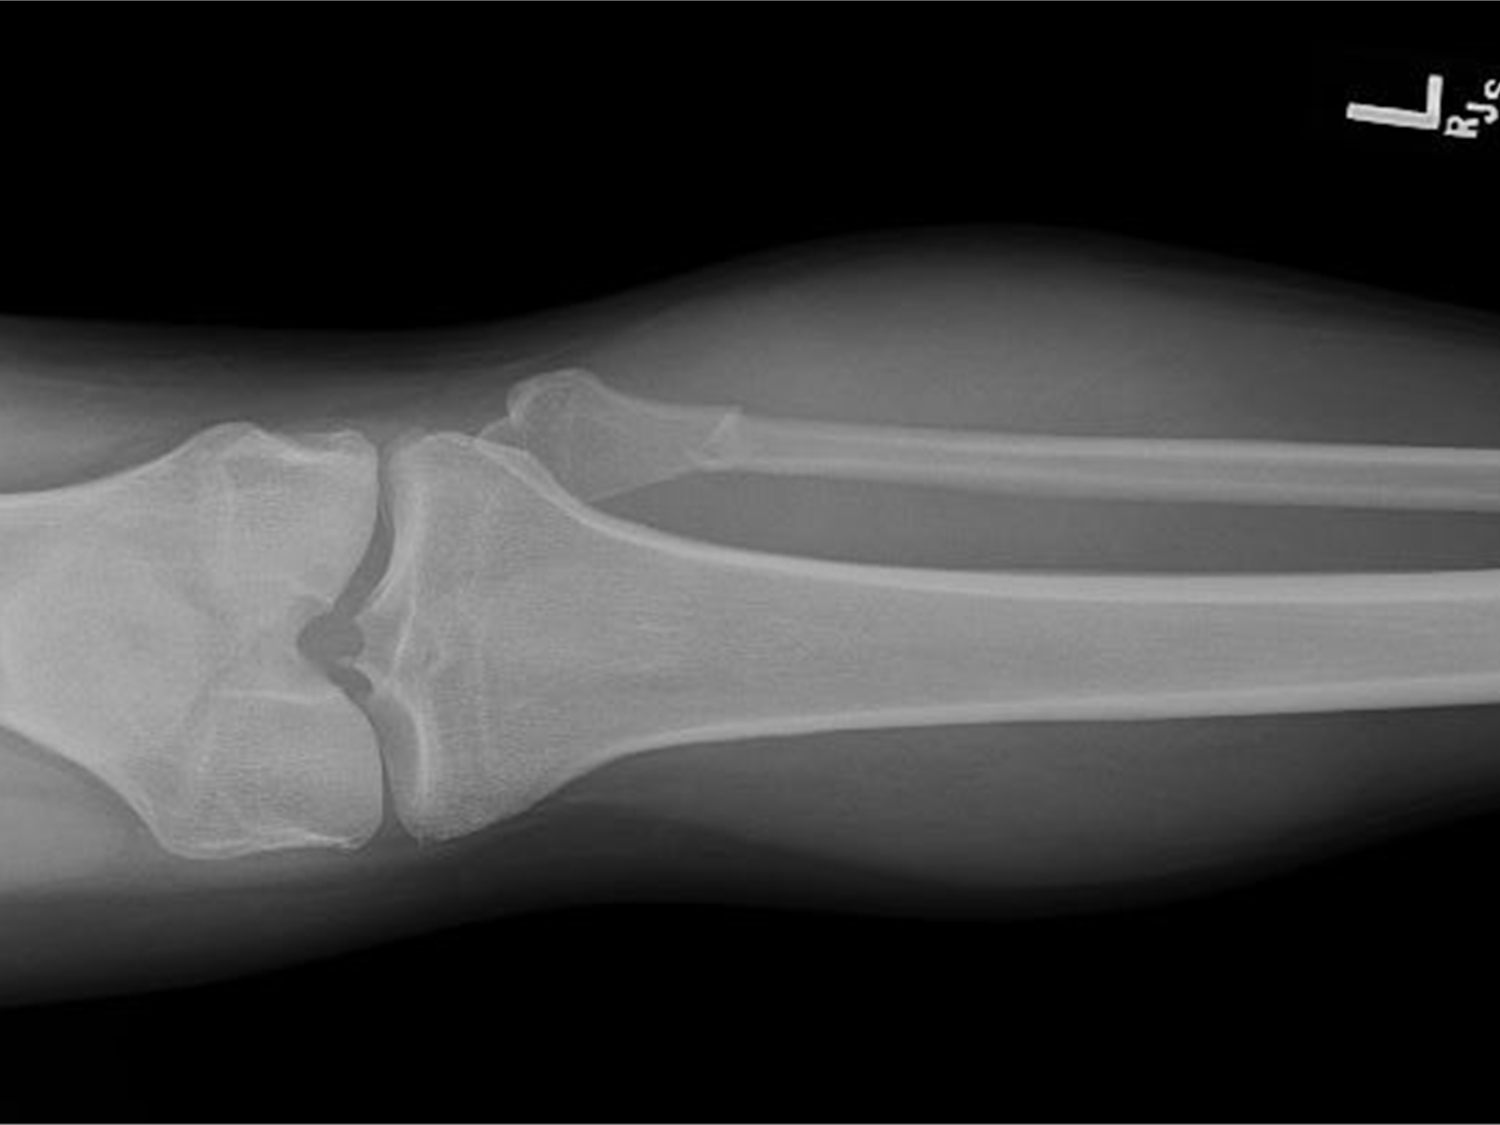

radius (top) ulna (bottom)

82